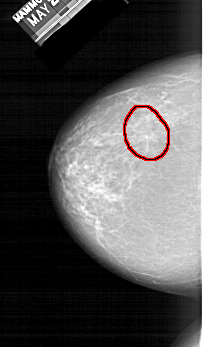

A_1410_1.LEFT_MLO

LEFT_MLO LINES 6256 PIXELS_PER_LINE 3166 BITS_PER_PIXEL 12 RESOLUTION 43.5 OVERLAY

FILE: A_1410_1.LEFT_MLO.OVERLAY

TOTAL_ABNORMALITIES 1

ABNORMALITY 1

LESION_TYPE MASS SHAPE ARCHITECTURAL_DISTORTION MARGINS ILL_DEFINED

ASSESSMENT 4

SUBTLETY 2

PATHOLOGY BENIGN

TOTAL_OUTLINES 1

BOUNDARY